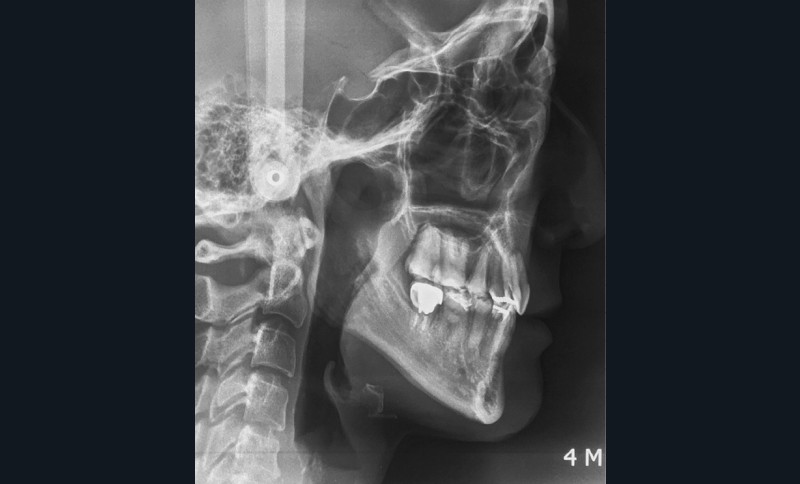

Sur le plan squelettique, on retrouve une classe III de Ballard par hypomaxillie, dans un schéma facial hyperdivergent.